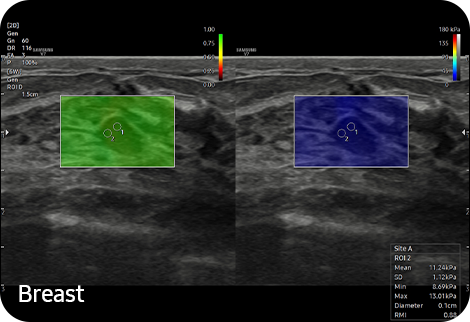

Display and quantify tissue stiffness

in a non-invasive method

S-Shearwave Imaging™ ¹ allows the non-invasive assessment of stiff tissues in various applications. The color-coded elastogram, quantitative measurements, display options, and user-selectable ROI functions are useful for accurate diagnosis.

Display tissue stiffness in color image

A diagnostic ultrasound technique for imaging elasticity, ElastoScan+™ observes the transformation of the tissue strain by the internal or external forces, and converts relative stiffness into a color image.